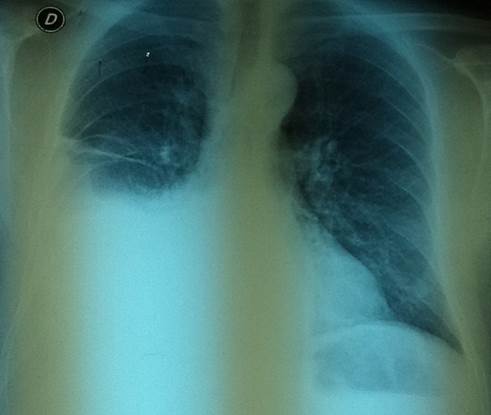

Dado los hallazgos a nivel pleuropulmonar se realiza radiografía de tórax que muestra opacidad homogénea en vidrio esmerilado en mitad inferior de campo pulmonar derecho con ascenso a axila que borra el espacio costofrénico derecho compatible con derrame pleural(Figura 1).